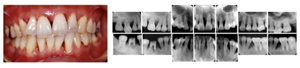

図8 長期メインテナンスの実際

1999年初診。年齢32歳 女性、“はぐきが腫れる”という主訴で来院されました。若い年齢にもかかわらず重度歯周炎にすでに罹患をしていました。

治療後21年。右上第1大臼歯は治療時に抜歯となってしまいましたが、治療完了後は定期メインテナンスを継続し、歯周組織は安定、一本の歯も失わずに現在まで経過しています。